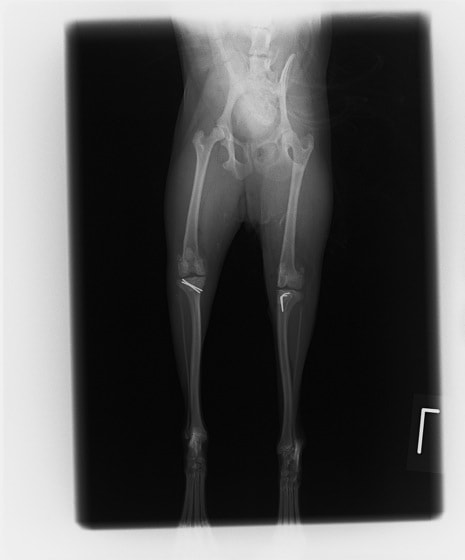

■ 症例22 ポメラニアン 1歳5か月 去勢雄

左後肢の挙上を主訴に来院した。整形学的検査、レントゲン検査より左右の膝蓋骨脱臼(左GradeⅡ〜Ⅲ、右Grade Ⅱ)を認めた。また、脛骨の前方引き出し試験の際に、引き出し兆候は認められないものの、疼痛が認められたため、前十字靭帯の損傷が疑われた。術中における、目視および関節内の操作によって、前十字靭帯の損傷や過伸展といった異常が認められなかったため、膝蓋骨脱臼の整復のみ実施した。手術手技は縫工筋及び内側広筋の解放、脛骨粗面の外側転位、滑車ブロック形造溝術、内外側関節包の縫縮を実施した。本症例は跛行もなく経過良好である。しかし、頸骨高平部の角度(TPA)が 右26.2°、左24.9°であり、解剖学的に前十字靭帯損傷のリスクが高いことから今後の経過に注意が必要である。